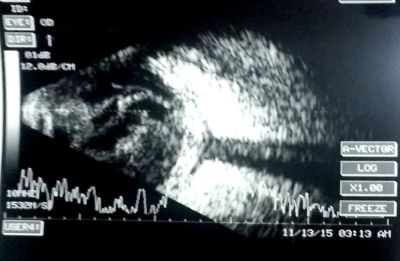

When an infectious etiology is suspected in the orbit, dilated fundus exam is deferred as it would interfere with identifying a new afferent pupillary defect, a critical orbital sign suggestive of progression. A Bright Scan Ultrasound (B-scan) can be used to visualize the posterior chamber of the eye to assess for vitritis (vitreous inflammation that present as vitreous echoes), exudative retinal detachment, scleritis (scleral thickening with classic “T-sign”), choroidal lesions (dome-shaped lesions), choroidal thickening, sub-tenon’s fluid, lens dislocation, lens edema, and shallow anterior chamber).

Bright-scan Ultrasonography (B-Scan)

B-Scan is a cost-effective, efficient modality to evaluate posterior segment lesions of the eye. It is particularly useful for assessment of the vitreous, posterior pole, sub-tenon’s space.